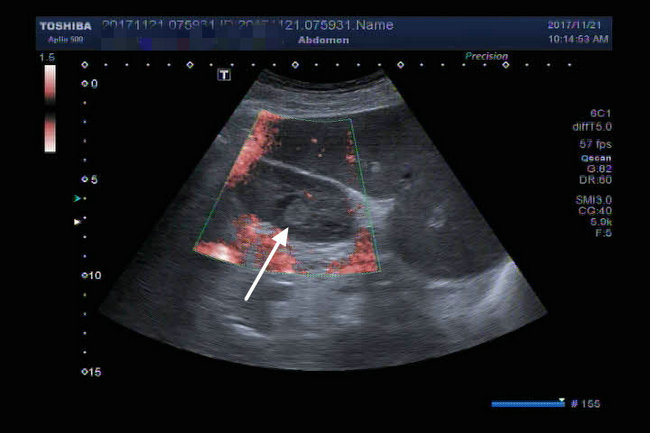

▲ 术前SCT、超声影像检查结果

由于肿瘤较小(1.2*1.4cm),位于左肾肾门处,被血管包围,位置隐蔽,常规超声检查很难发现。超声诊断科主任杨青教授及其精英团队术前反复检查,模拟术中精确定位。术中督导,精确定位,给手术提供动态精准的三D指导,保证了左肾小肿瘤的外科精准切除,术后检查标本肿瘤完整,与术前CT、超声检查符合,术后病理报告:(左)肾透明细胞癌,Fuhrman 1-2级,肿瘤包膜完整,切缘未见癌波及。